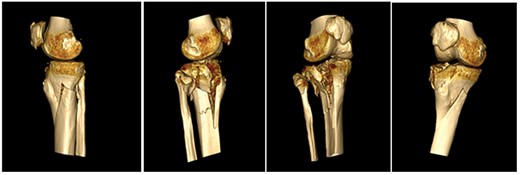

This case report follows a 67-year-old gentleman who sustained a Schatzker VI fracture of his right tibia after falling 2 m from a ladder (Fig. 6). The injury was closed and neurovascularly intact; he was managed initially in a neighbouring health board with a bridging external fixator because of the high degree of comminution. He was referred to the current institution; and at a routine review 3 weeks post-injury, it was noted that a pin had fractured. The external fixator was removed, and he was converted into an above knee cast. He progressed to a Sarmiento cast and then a range of motion brace at 12 weeks. Partial weight bearing was permitted, and he received physiotherapy. He was kept under regular review and the fracture had united (Fig. 7); he was noted to have a range of movement of 10°–60° with healed pin site wounds. At 8 months post-injury, he underwent total knee arthroplasty utilizing a posterior stabilised Depuy Synthes (Warsaw, In) Attune revision tibial metaphyseal sleeve and stem, and femoral component without sleeve or stem. The patient had an uncomplicated recovery and kept under routine review in the outpatient clinic. At 6 months’ review, the patient had a range of motion of 0°–105°, fully healed wound and reported a significant improvement in pain. The patient used no walking aids, and the Oxford Knee score was 40 (Fig. 8).